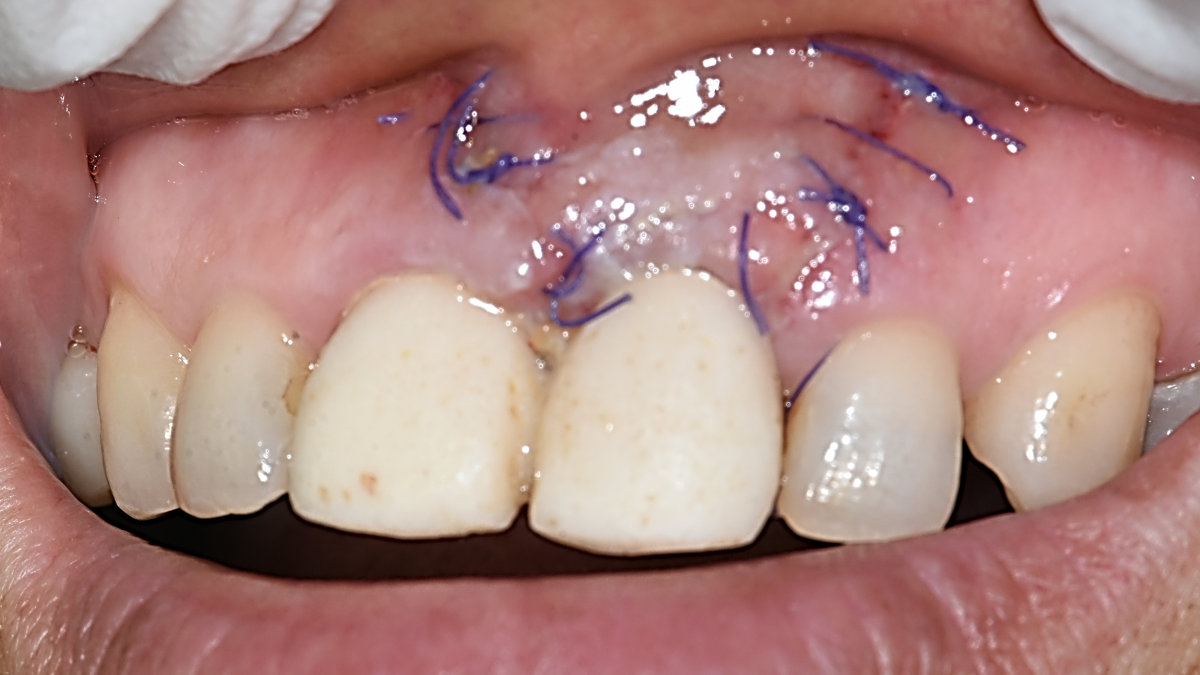

Apicorctomy /central incisor /GBR ; 6-year follow up.

<CJ SBN> Apicorctomy /central incisor /GBR ; 6-year follow up.